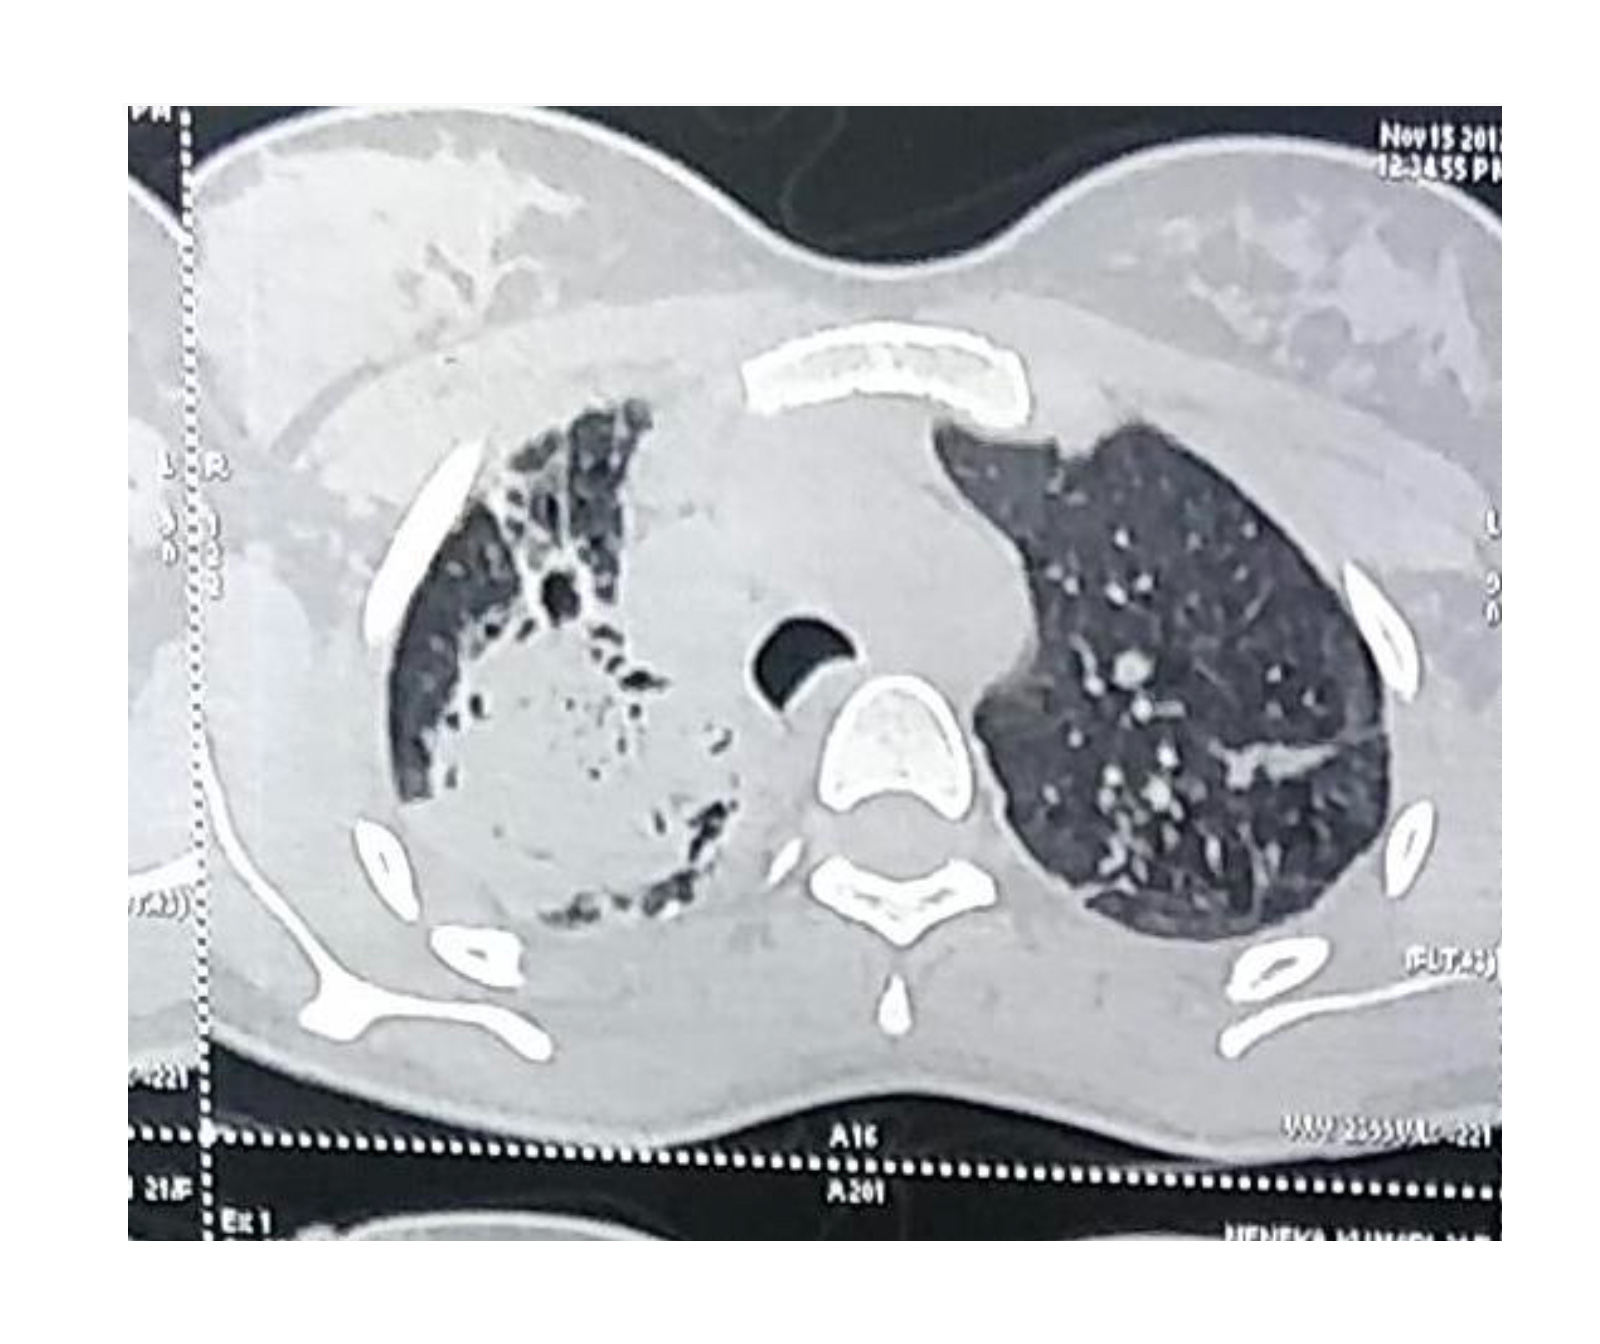

MDR TB is a form of tuberculosis caused by bacteria that are resistant to at least two of the most effective anti-TB drugs. This resistance makes MDR TB more challenging to treat and control compared to drug-susceptible TB.

When TB infection damages the lungs, it can lead to the formation of scar tissue or cavities. These structural changes can weaken blood vessels in the lungs, making them more prone to bleeding. Hemoptysis can occur when these blood vessels rupture, causing blood to be coughed up.

When it comes to Multidrug-Resistant Tuberculosis (MDR-TB), the decision to pursue surgical treatment is typically made on a case-by-case basis. MDR TB is caused by strains of the bacteria that are resistant to at least two of the most powerful anti-TB drugs. It is a serious condition that requires comprehensive treatment.

Surgery may be considered as an adjunct to medical therapy in certain situations. For example, if there is a localised area of infection that is not responding well to medication, surgery may be recommended. Additionally, surgery may be considered for the removal of lung cavities or to address complications such as hemoptysis (coughing up blood).

Highly skilled Surgical Intervention: Dr Pallavi Purwar can perform surgical procedures such as lung volume reduction surgery to improve lung function and quality of life for individuals with severe scarring.